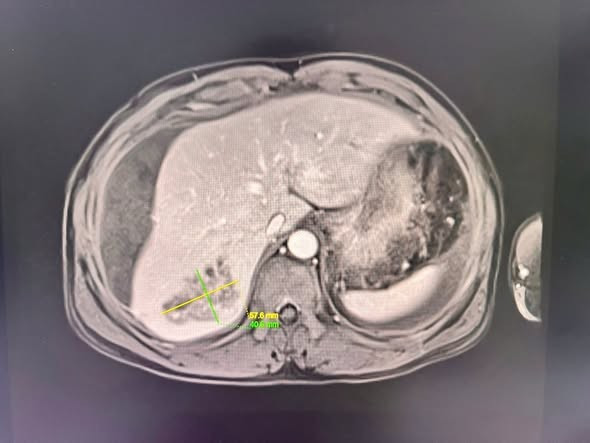

Bệnh nhân T.V.L 46 tuổi, huyện Quỳnh Lưu, tỉnh Nghệ An, nhập viện trong tình trạng mệt mỏi, đau bụng vùng quanh rốn và hạ sườn phải, bụng chướng căng. Kết quả chụp CT Scanner và MR ổ bụng cho thấy hình ảnh tổn thương gan Phải hướng đến áp xe gan đã vỡ, chảy máu trong ổ bụng lượng nhiều.

Hình ảnh ổ áp xe vỡ trên phim chụp CT - Ảnh BVCC

Trong quá trình can thiệp, các bác sĩ phát hiện ổ áp xe gan vỡ kích thước 57,6mm x 40,6mm, có nhiều ổ giả phình, nhiều dịch máu và mủ tràn ổ bụng. Sau can thiệp, tình trạng bệnh nhân ổn định, dấu hiệu sinh tồn tốt.